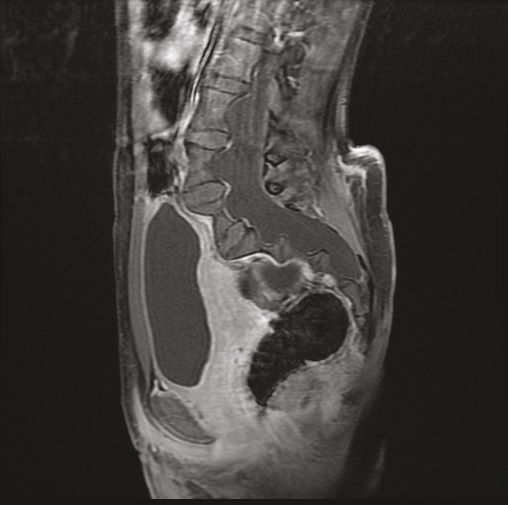

Cette jeune patiente de 12 ans atteinte d’une neurofibromatose de type 1 consultait pour des lombosciatalgies gauches. L’échographie pelvienne montrait une formation latéro-utérine droite cloisonnée. L’imagerie par résonance magnétique (IRM) pelvienne notait la présence d’une ectasie durale (fig. 1 ) responsable d’un festonnage (scalloping) [fig. 2 ] des parois des vertèbres lombosacrées, de même signal que le liquide céphalorachidien en hyposignal T1, hypersignal T2, sans rehaussement après injection de chélates de gadolinium, associée à des méningocèles élargissant les trous de conjugaison (fig. 1 ), fusant à travers les foramens intervertébraux en regard de L5 avec une extension paravertébrale antérieure. En l’absence de signe déficitaire, un traitement antalgique avec surveillance était prescrit, suivi d’une amélioration clinique.

Dans la neurofibromatose de type 1, l’ectasie durale est attribuée à une dysplasie mésodermique primitive des méninges. L’expansion des méninges sous l’effet des pulsations du liquide cérébrospinal provoque un scalloping sur la face postérieure des corps vertébraux et des hernies du sac méningé au travers des foramens intervertébraux.1 Le scalloping est observé dans la neurofibromatose dans 10 % des cas1 mais également dans le syndrome de Marfan, le syndrome d’Ehlers-Danlos et dans la spondylarthrite ankylosante. L’élargissement du canal rachidien et des foramens, la cyphose, la scoliose peuvent s’y associer.1 Les complications sont des déformations et dislocations vertébrales. Un déficit neurologique est rare.2